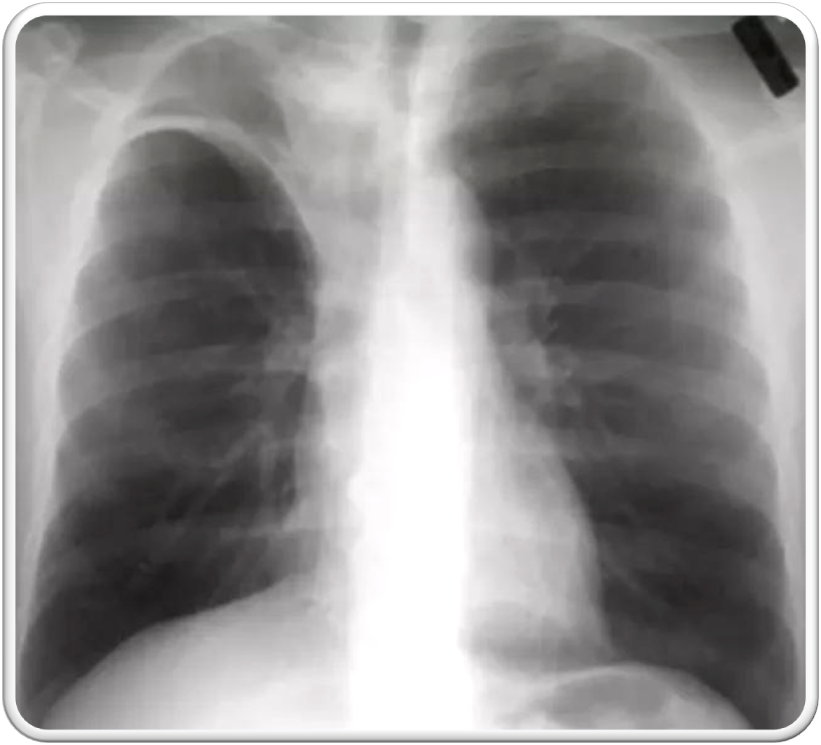

shows a right upper lobe airspace opacity adjacent to the trachea.

• ⁠ ⁠focal or patchy heterogeneous consolidation involving the apicoposterior segments of the upper lobes and the superior segments of the lower lobes

lateral view of the same patient, the typical location of the apicoposterior segment